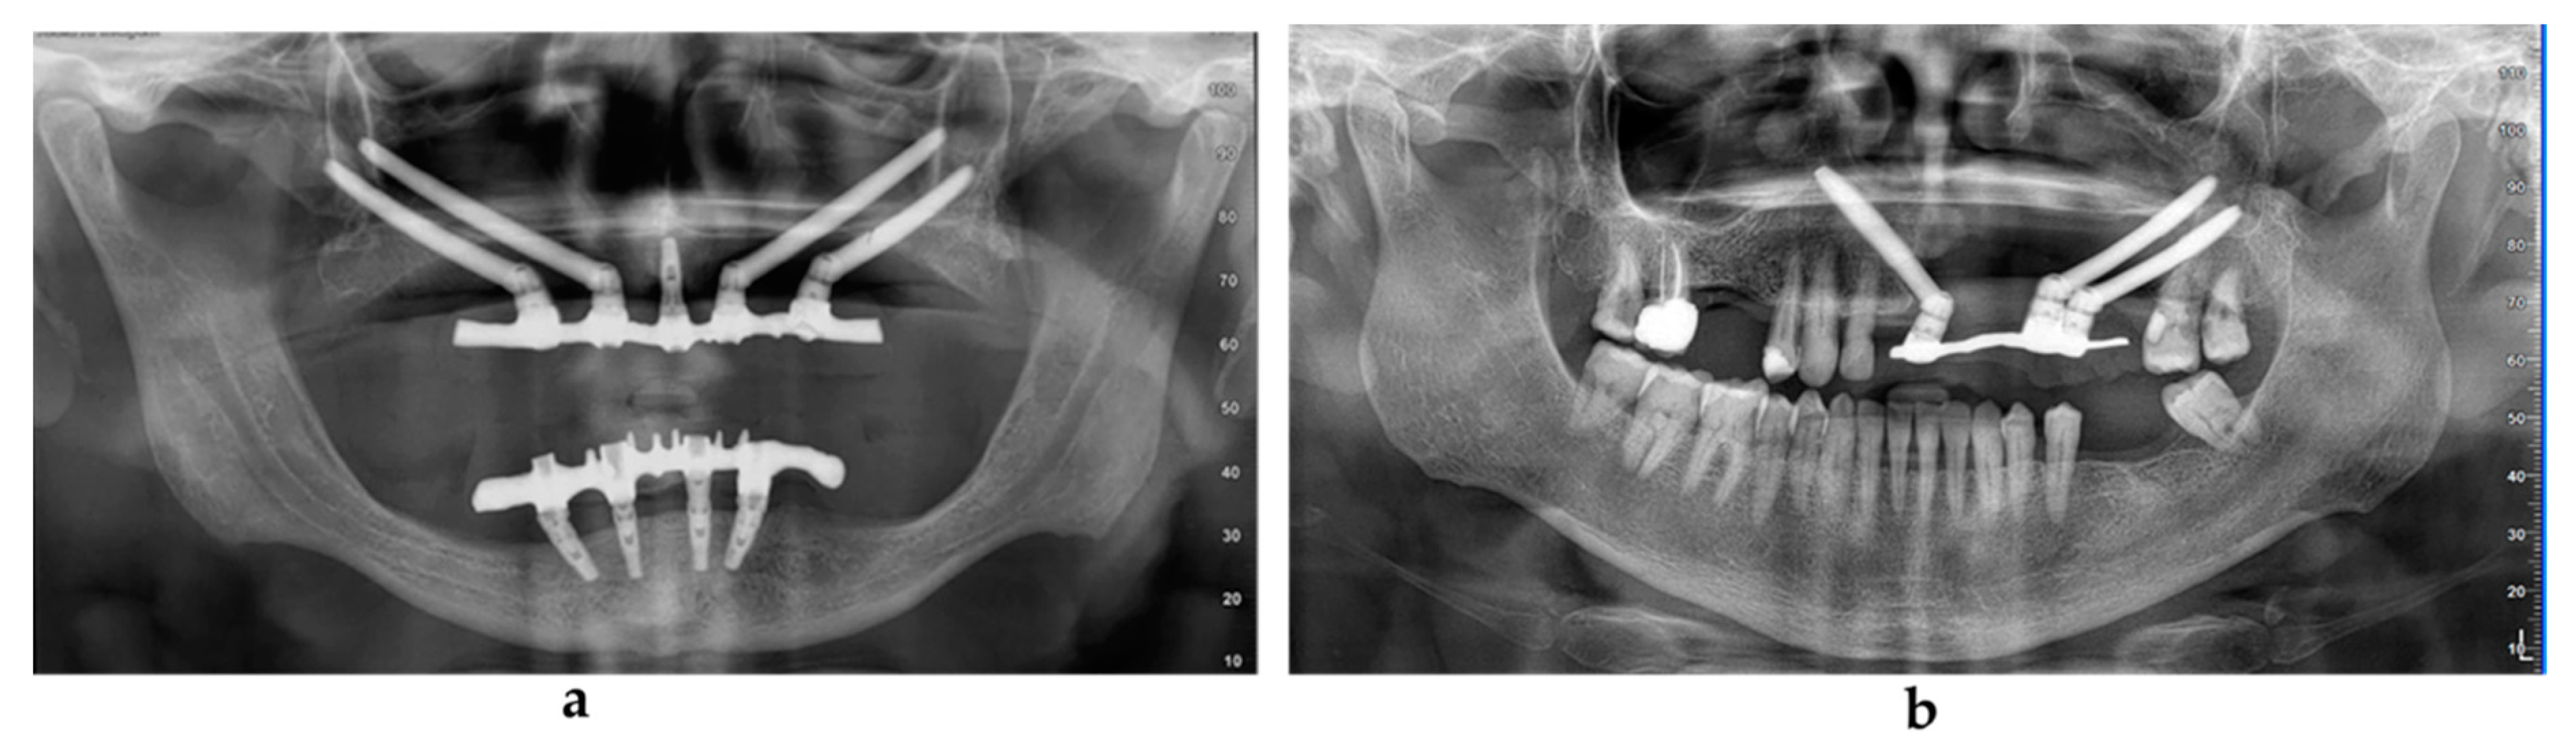

Radiologic examination included an orthopantomographic examination (Figure 5a,b) every year and a lateral teleradiographic examination after implant loading. A CBCT examination was performed at 1 year after the surgery and was repeated if needed. All patients underwent a strict professional hygiene maintenance protocol with 3-month recalls. Instructions and devices for maintaining proper oral hygiene at home were provided to the patients.

Figure 5. Orthopantomographic evaluation at 4 and 5 years after the surgery in the atrophic group (a) and in the oncologic group (b).